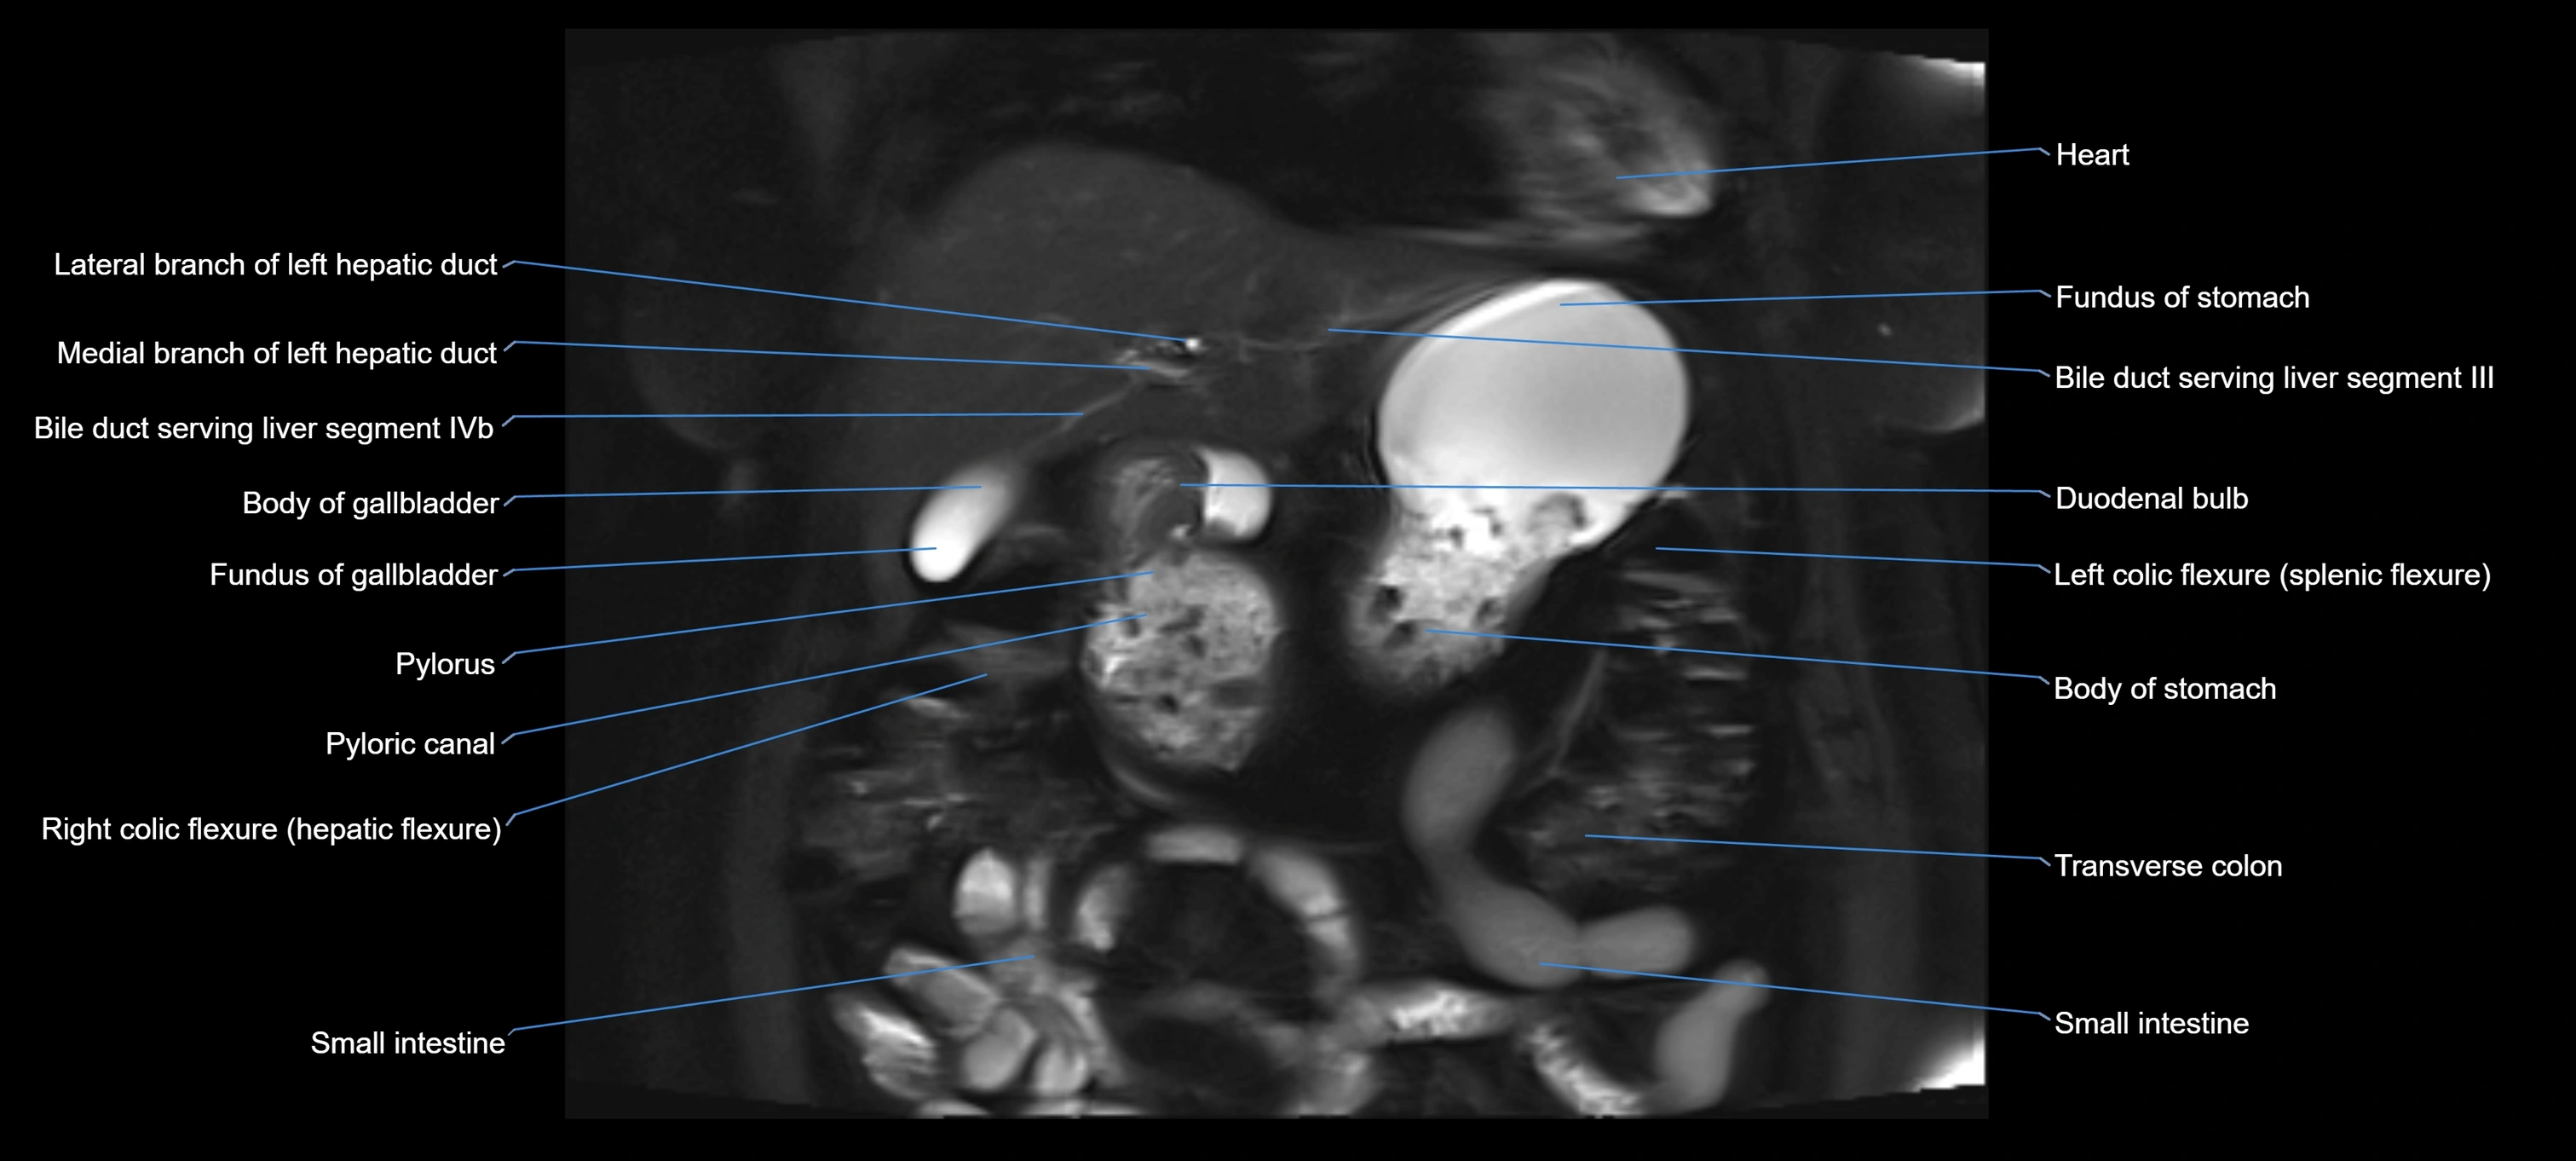

MRI image

image

Fullscreen Image